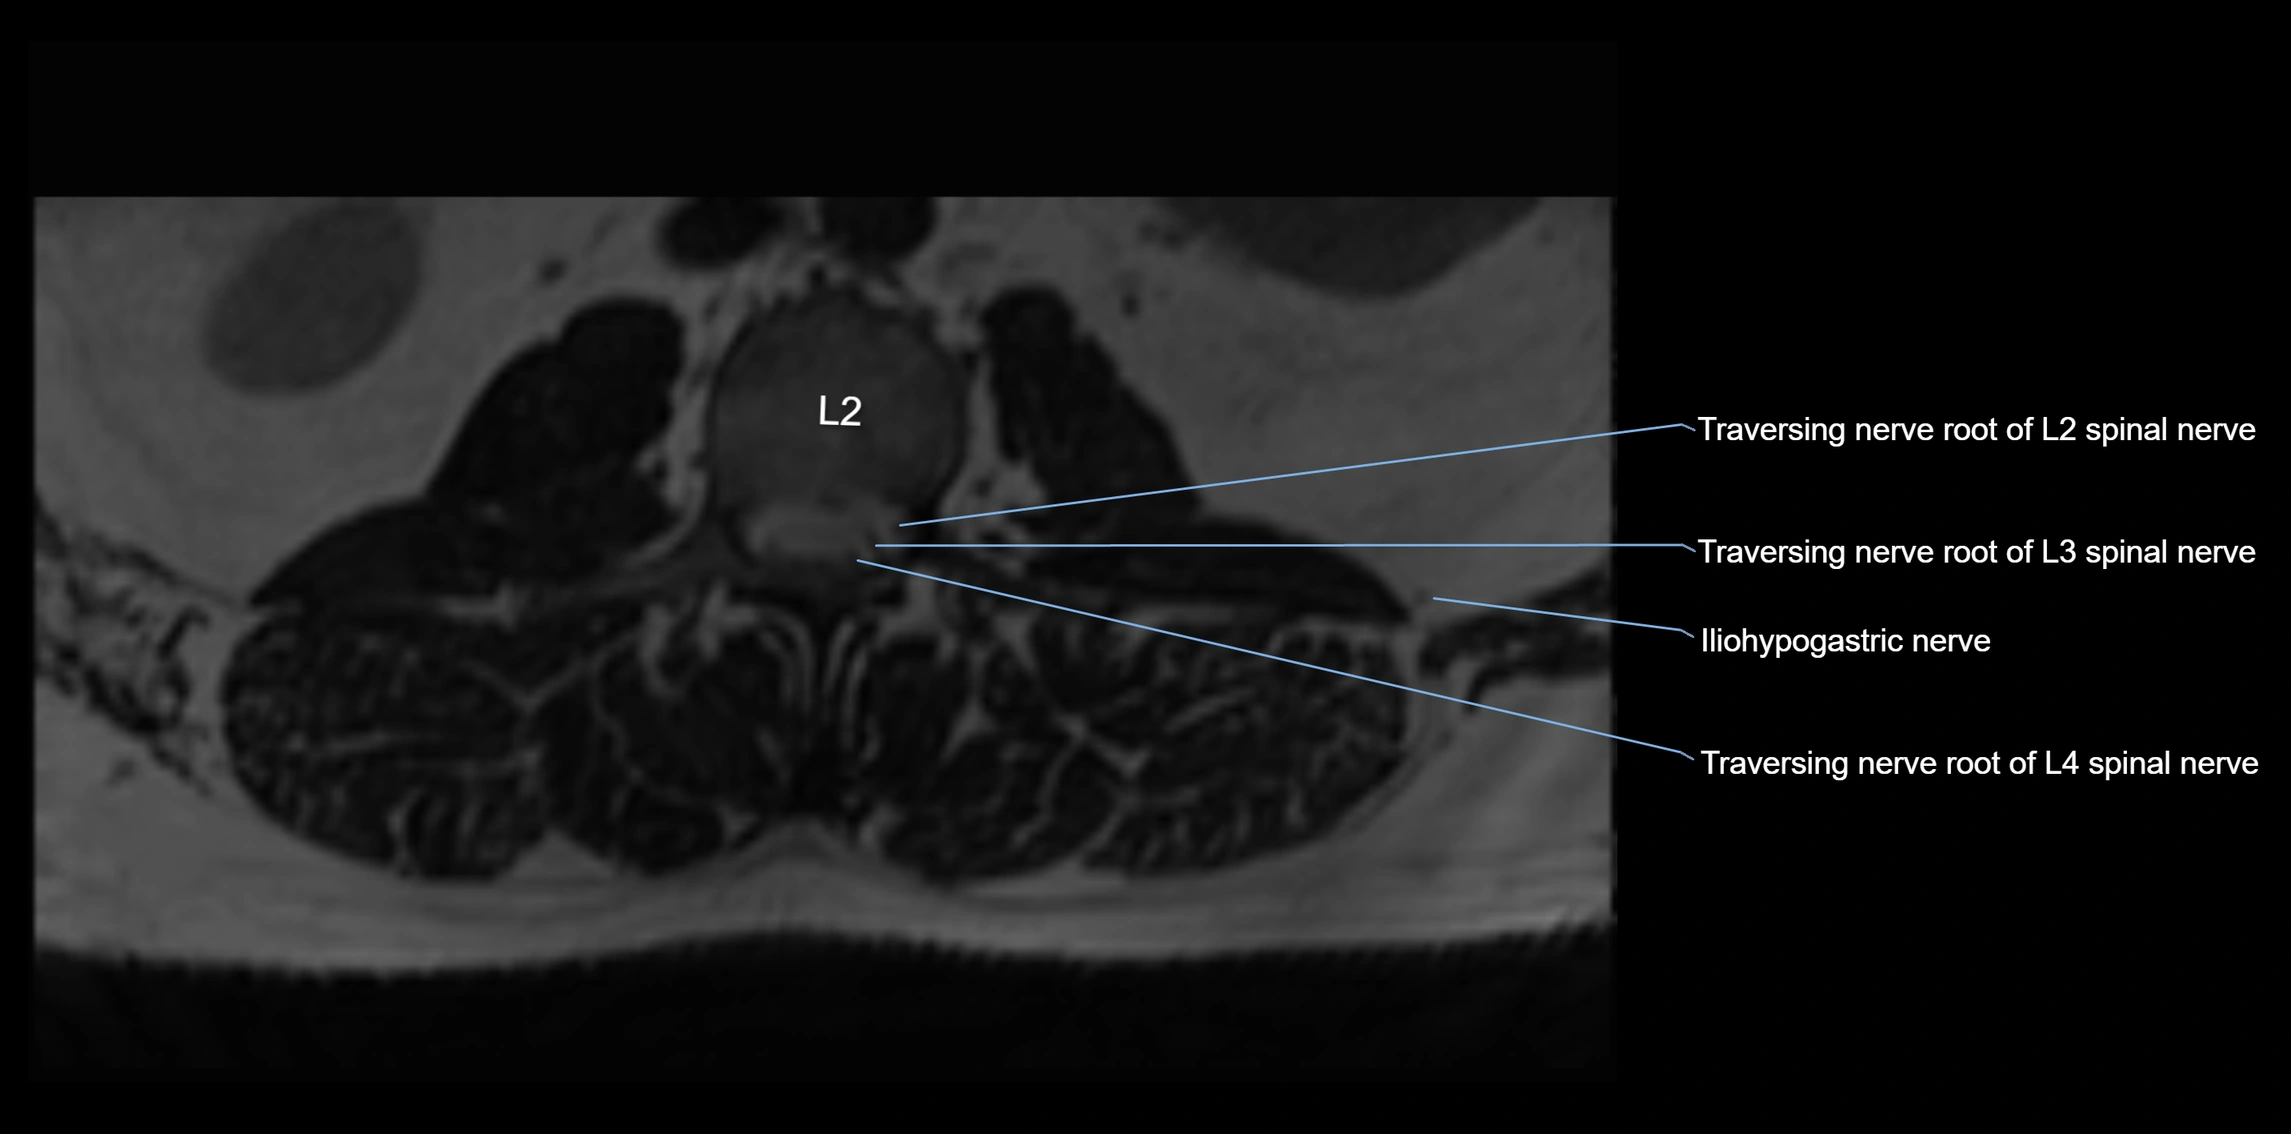

MRI Appearance

T1-weighted images:

• Nerve appears as a very thin low-to-intermediate signal intensity structure

• Surrounded by bright fat, aiding visualization

T2-weighted images:

• Nerve shows intermediate to mildly hyperintense signal compared to muscle

• Pathological involvement appears brighter

3D T2 SPACE / CISS:

• Nerve appears intermediate to mildly hyperintense compared to muscle

• Surrounded by bright fat or CSF, improving visualization

• Best sequence for mapping small pelvic nerves such as the anococcygeal

MRI image

image